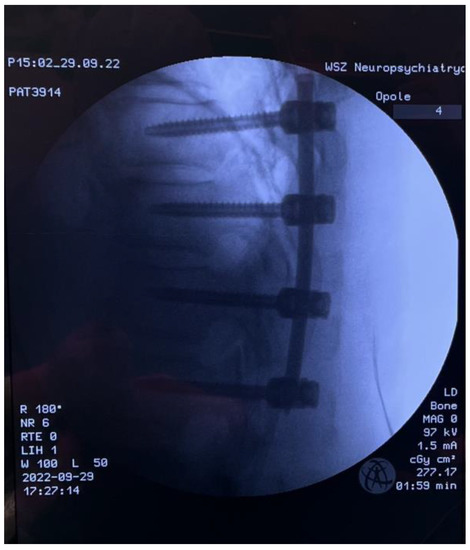

Fully Endoscopic Spine Separation Surgery in Metastatic Disease—Case Series, Technical Notes, and Preliminary Findings

2. Materials and Methods

3. Results